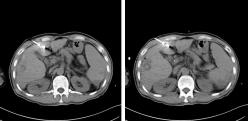

今年4月,张叔上腹增强CT检查显示:肝硬化,肝门区及腹主动脉旁淋巴结增多、部分增大,结合患者多年乙肝肝硬化病史,诊断为“发性肝癌IV期”。张叔早知他是乙肝患者,但不曾料到自己正值壮年就已患上肝癌。经同乡介绍,今年6月,张叔来到广州复大肿瘤医院进行氩氦刀冷冻消融术及肝门静脉癌栓125碘粒子植入术,术程顺利,手术创口仅约2mm,术后患者感觉良好,生命体征平稳,治疗效果良好,随即出院返回四川乡下(详情百度搜索:广州复大医院案例)。

12月初,张叔再次来到医院就诊。考虑肝左叶肿瘤性病变。综合患者各项生理指标,为控制肿瘤病灶的进一步增大,以牛立志教授为首的专家团队建议他进行微波消融治疗。因为张叔的血小板只有5万多,而氩氦刀冷冻消融会消耗血小板,这种情况出血风险比较大,而微波消融对血小板影响小,对肝硬化失代偿的患者来讲可以争取更多的抗肿瘤治疗机会。

12月14日张叔在B超加CT引导下行肝脏肿瘤微波消融治疗,过程顺利,术中消融区域定位准确,消融范围满意,术后未诉不适,生命体征平稳,术后恢复良好,并且在术后第三天出院回家。